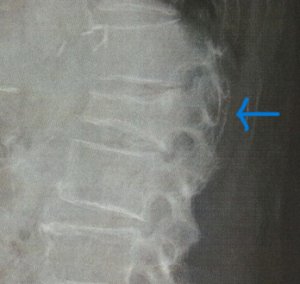

脊椎圧迫骨折は背骨の椎体と呼ばれる部位の骨折です。下のレントゲン写真に示すように四角い骨がつぶれて長方形になるのですが、しりもちをついたりしてその衝撃で骨折することが多く、またくしゃみや咳でも発症します。また骨粗鬆症が進行している方はきっかけがなく自然に発症することもあります。